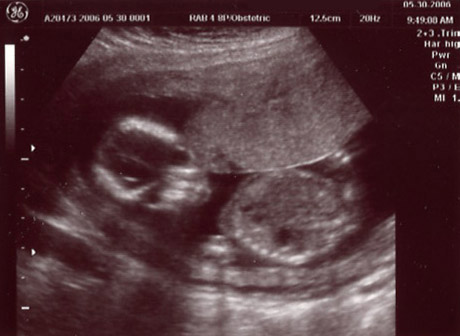

| May 30, 2006 - Sixteen Week Ultrasound! |

| Jen was feeling some pain this morning (May 30th), so to play it safe, she called her doctor. They said to come right in. We were obviously concerned, but they saw us right away and asked her a bunch of questions. They didn't think it was anything to be concerned with, but they

performed an ultrasound just in case. That too checked out and we left a bit relieved and happy to have even

more pics of our yet to be born angel. ~Chris |

Head on face shot |